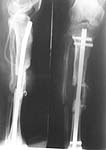

I do not think closed nailing would have been possible in this case. In fact I can say it positively now since we took this case for surgery today. Both the ends of the nonunion site were sclerosed. Inthe proximal end of canal was easily opened by resecting a little bone. But on the distal side bone had to be resected for about 3cm before any semblance of canal could be seen. This had to be initially drilled with a small drill bit and then gradually enlarged. So an attempt at closed nailing could not have succeded at all.

What we did today: Open resection of nonunion followed by open interlocking nail using solid nail. The gap was interposed with vascularised fibula from the opposite leg using microvascular anastomosis. In fact my colleague who did the microvascular surgery had to struggle since the vessels in this diabetic patients was atherosclerotic. I have just returned after this long surgery and as it stands the stability is good and the flap vascularity is good. Pray and hope that this will be the last surgical interference this patient will require. I will try to attach the post op x-ray picture.